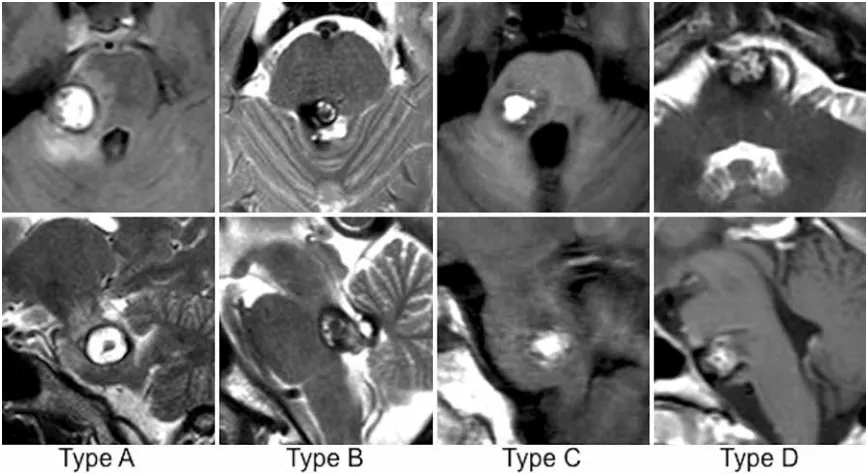

多年来,神经外科医生一直在寻找更安全的手术通道。INC巴特朗菲教授在本研究中根据最合适或可能的手术入路定义了4种不同病变类型(A-D型)脑桥海绵状血管瘤。

每列显示一名具有代表性脑桥海绵状血管瘤类型患者的轴向(上)和矢状(下)MR图像。

A型

病灶贴在脑桥外侧,只能从侧面切(后外侧入路),从中间切会伤脑干;

B型

病灶靠近脑桥后方的菱形窝(第四脑室底),只能从中间切(后内侧入路);

C型

病灶夹在外侧和中间之间,两种入路都能切(研究的核心对象);

D型

病灶长在脑桥前面,得从前面绕进去(前外侧入路)。

最引人关注的是C型病变——它既可从后外侧也可从后正中入路处理,占所有患者的57%。